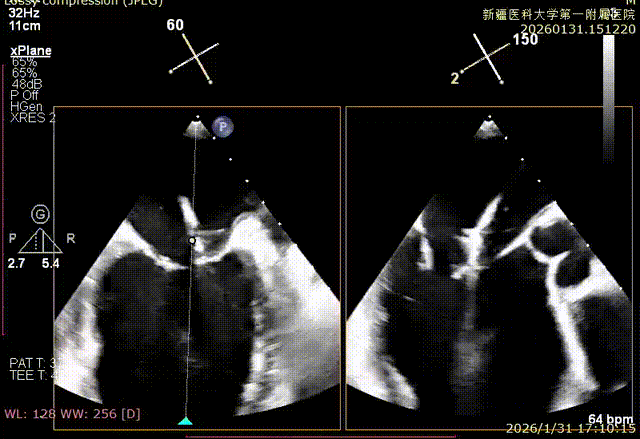

成功捕捞瓣叶并夹持

缓慢关紧夹臂

双孔组织桥稳定

3D enface反流充分降低

术后平均跨瓣压差1mmHg